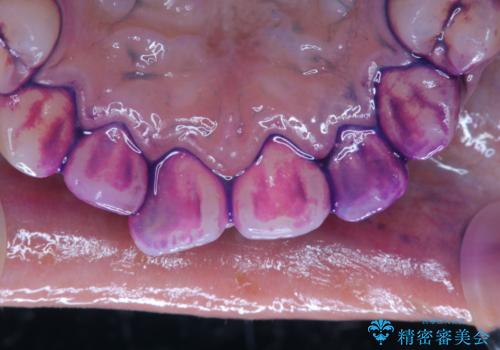

口腔内にはたくさんの細菌がいるため、ヌルヌルとしたプラーク(歯垢)が自然に歯の表面に付きます。

このプラーク(歯垢)にはたくさんの細菌が潜んでおり、虫歯や歯周病・口臭などの最大の原因です。そのため、毎日の歯磨きでプラーク(歯垢)をキレイに取り除くことが、健康な歯を保つためには欠かせません。

しかし、プラークは歯の色と似ているため、見ただけでは付着しているかどうかがハッキリとは分かりません。

染め出し液を使ってプラークを染め出すことにより、普段の歯みがきで磨き残している場所を目で確かめることができます。